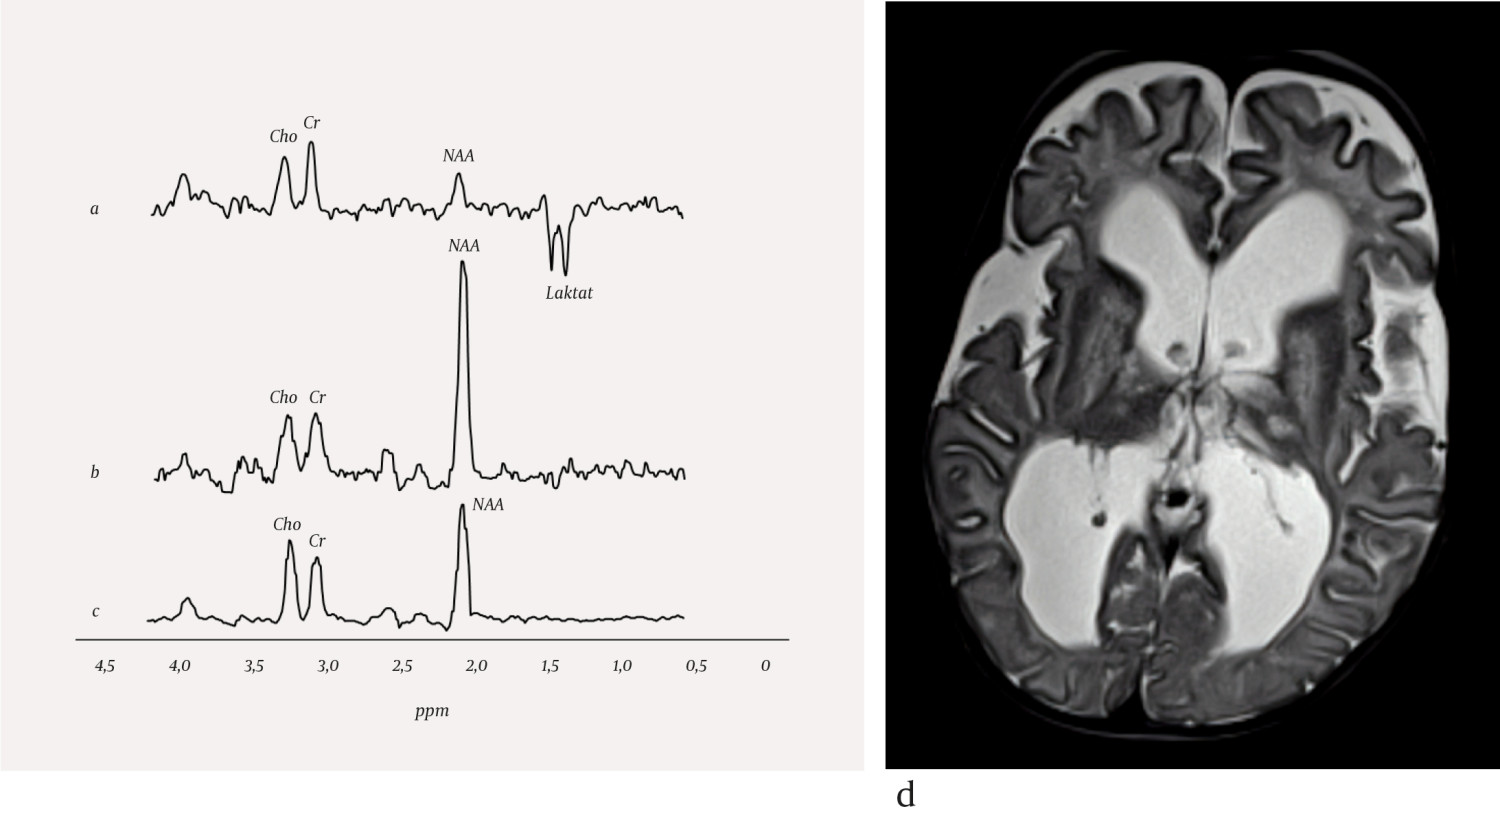

Det er i store trekk de samme teknologiske og fysiske prinsippene bak MR-spektroskopi som bak MR-bildedannelse. Protoner (hydrogenkjerner) har magnetiske egenskaper i et sterkt magnetfelt og er kilde til signalene ved begge metoder. Alle protoner i et vannmolekyl vil ha like magnetiske egenskaper, og de utgjør den viktigste kilden til signal ved MR-avbildning. Protoner i forskjellige molekyler har litt forskjellige magnetiske egenskaper, og denne forskjellen gjør at små molekyler i kroppen kan detekteres med MR-spektroskopi. Et MR-spekter vil derfor vise molekyler i vev, forutsatt at molekylene er mobile og til stede i en målbar mengde (> 1 mmol/l) (1). Molekyler differensieres av frekvensforskjeller langs x-aksen, mens toppenes areal tilsvarer konsentrasjonen av molekylet (figur 1). Enkelte sykdommer kan karakteriseres med MR-spektroskopi, enten gjennom påvisning av molekyler som normalt ikke ses i friskt vev, eller ved at den relative konsentrasjonen av metabolitter er ulik den man ser i tilsvarende friskt vev (1, 2). I tillegg til vannsignalet er de dominerende toppene i MR-spektre av hjernen fra kreatin, kolin og N-acetylaspartat. Avhengig av undersøkelsesbetingelsene kan man også påvise metabolitter som har lavere konsentrasjoner i normalt hjernevev, som myo-inositol og glutamin/glutamat. I normalt hjernevev er mengden laktat vanligvis for lav til å kunne påvises med MR-spektroskopi, mens lipider er bundet i faste, immobile strukturer og kan derfor normalt ikke detekteres med denne teknikken.

Nevrometabolske sykdommer utgjør en stor og heterogen gruppe medfødte tilstander. Insidens for disse tilstandene enkeltvis er svært lav, mens samlet insidens er estimert til å være 1 per 800–2 500 fødsler (3, 4). De fleste pasienter med nevrometabolsk sykdom har forsinket utvikling eller nevrologiske symptomer og tegn som nyfødt eller i tidlig barnealder. Unntaksvis kan nevrometabolske sykdommer også debutere i voksen alder. Mange nevrometabolske sykdommer gir uspesifikke strukturelle forandringer i sentralnervesystemet som kan karakteriseres med MR-avbildning, men det kan være vanskelig å stille en sikker diagnose kun fra bildefunn. For enkelte nevrometabolske tilstander kan derfor MR-spektroskopi være nyttig på grunn av evnen til å beskrive hjernevevets sammensetning av metabolitter. Noen få sykdommer har en helt sykdomsspesifikk profil ved MR-spektroskopi (5), mens andre har en MR-spektroskopi-profil som kombinert med bildefunn og resultater av kliniske undersøkelser er spesifikk for tilstanden (2). Vanlige endringer i patologiske MR-spektre er redusert mengde N-acetylaspartat, redusert eller økt mengde kolin, økt mengde myo-inositol og tilstedeværelse av laktat. Eksempler på nevrometabolske sykdommer som MR-spektroskopi kan bidra til å karakterisere, er mitokondrielle sykdommer og enzymatiske defekter (figur 1a og 1b).

Enzymatiske defekter kan medføre svikt i cellulære prosesser dersom et spesifikt enzym mangler eller er defekt. Alvorlighetsgrad avhenger av hvilket enzym som er defekt, og det kliniske bildet ved sykdommer i denne gruppen er høyst varierende. Canavans sykdom er en leukodystrofi, hvor hvit substans blir ødematøs, og det dannes væskefylte hulrom (figur 1d). Pasienter med Canavans sykdom har spesifikke genmutasjoner som medfører mangel på enzymet aspartoacylase, som er essensielt for spalting av N-acetylaspartat til aspartat og acetat. Enzymmangelen medfører opphoping av N-acetylaspartat i hjernen og hindret syntese av myelin. Den vanligste formen av sykdommen opptrer ved seks måneders alder og gir omfattende svikt i nevrologiske funksjoner (6). Sykdomstegn er irritabilitet, hypotoni og dårlig overkroppskontroll. Sykdommen medfører sterkt redusert utvikling hos barnet, og kan gi økt hodeomkrets, dårlig øyemotorikk, blindhet, epilepsi, muskelstivhet og spasmer. Forventet levetid er omkring ti år. MR-spektroskopi av pasienter med Canavans sykdom viser sterkt forhøyet signal fra N-acetylaspartat (figur 1b). Canavans sykdom er eneste kjente metabolske sykdom som medfører en økning i mengde av N-acetylaspartat.

Mitokondriesykdommer er en heterogen sykdomsgruppe som gir progressiv eller intermitterende hjerneskade (7). MR-avbildning viser varierende funn med ødem og vevsdestruksjon, men bilateral affeksjon av basalgangliene er typisk. Sammen med MR-avbildning og kliniske funn kan MR-spektroskopi bidra til å identifisere og karakterisere mitokondrielle sykdommer. Det mest gjennomgående funnet ved MR-spektroskopi er tilstedeværelse av laktat på grunn av endret intracellulær energiproduksjon, ofte fulgt av redusert N-acetylaspartat, som indikerer celletap. Leighs syndrom er en mitokondriopati som kan gi utviklingsforsinkelse, spastisitet og hjernestammedysfunksjon. MR-avbildning viser typisk symmetriske signalforandringer i basalgangliene, thalamus og hjernestammen. Laktat i MR-spektre fra disse områdene styrker mistanken om Leighs syndrom (figur 1a).